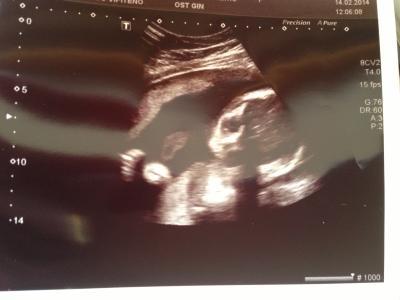

Bin auch wieder zurück vom FA! Gebärmutterhals hat sich zum glück nicht weiter verkürzt, ist gleich geblieben! Naja und aus der Maus ist heute dann plötzlich ein Junge Geworden, den "Zipfel" hab ich schon bevor er etwas sagte gesehen.... er meinte jedoch dass das dann beim nächsten US wieder anders aussehen könnte u es doch ein Mädchen wird, hat gesagt meist wenn die Eltern es wissen möchten dann sieht mans nicht so richtig! Ansonsten ist alles gut, hab nur leider kein schönes Bild bekommen, ist so blöd gelegen... aber egal :O)! Ach ja noch die heutigen Werte: BIP: 67 AU: 204 FE: 49 Lg und schönes Wochenende

Über die Maße war ich auch sehr erstaunt, dass die in einer Woche so viel wachsen.... Naja eigentlich ist es egal was es wird, Hauptsache gesund, aber stimmt, das hin und her ist wirklich doof :O) Kannst du mir vielleicht mein US Bild erklären :O)?? Sieht mich das kleine an und dann ist ein Arm und die Nabelschnur zu sehen stimmt das (wegen der Nabelschnur hat der Arzt mir gesagt)????, sieht eher nach einem Alien aus :O)

Ja das guckt dich an. die dunklen flecken sind die Augen Nabelschnur ist schwer zu sagen was es ist. Dieses gekrümmte links neben dem Gesicht könnte die sein.